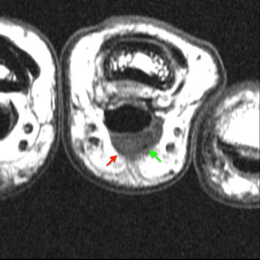

B - IRM du doigt, coupe axiale T2 : la masse est ovoide, de signal intermédiaire.

C - IRM du doigt, coupe axiale T1 : La masse est de signal intermédiaire. Présence d'une image punctiforme de bas signal (hémosidérine ?).

D - IRM du doigt, coupe axiale T1 gadodilinium, fat sat : Prise de contraste de la formation.

Tumeur à cellules géantes développée au niveau de la face palmaire du doigt.